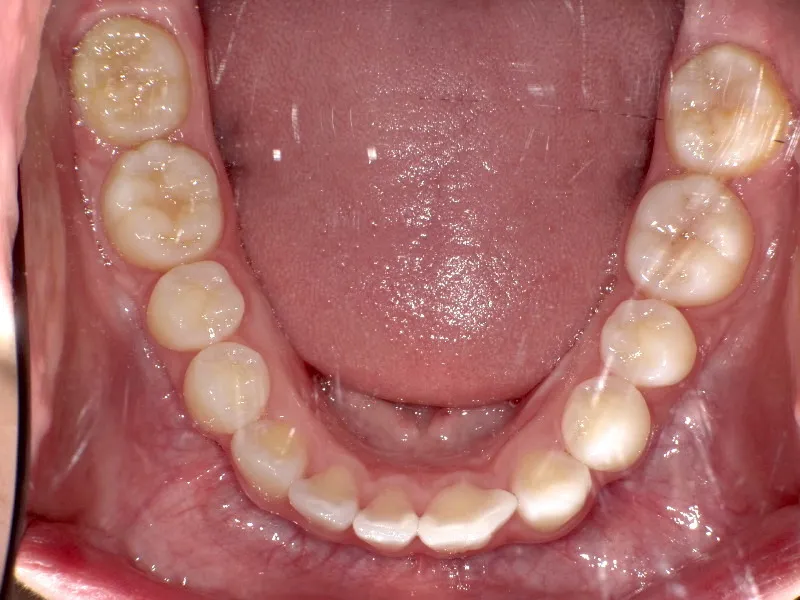

上下ガタガタで、下の歯は癒合歯(2本がくっついて1本の歯)です。

治療前と治療後で下の歯の銀歯がなくなっています。

これは銀歯の第1大臼歯を抜いて第2大臼歯、第3大臼歯の親知らずを使いました。

コルチコトミーという矯正法で歯根への負担を軽減しながら治療しました。

治療回数71回、3年5ヶ月の治療期間で矯正治療を終了しました。